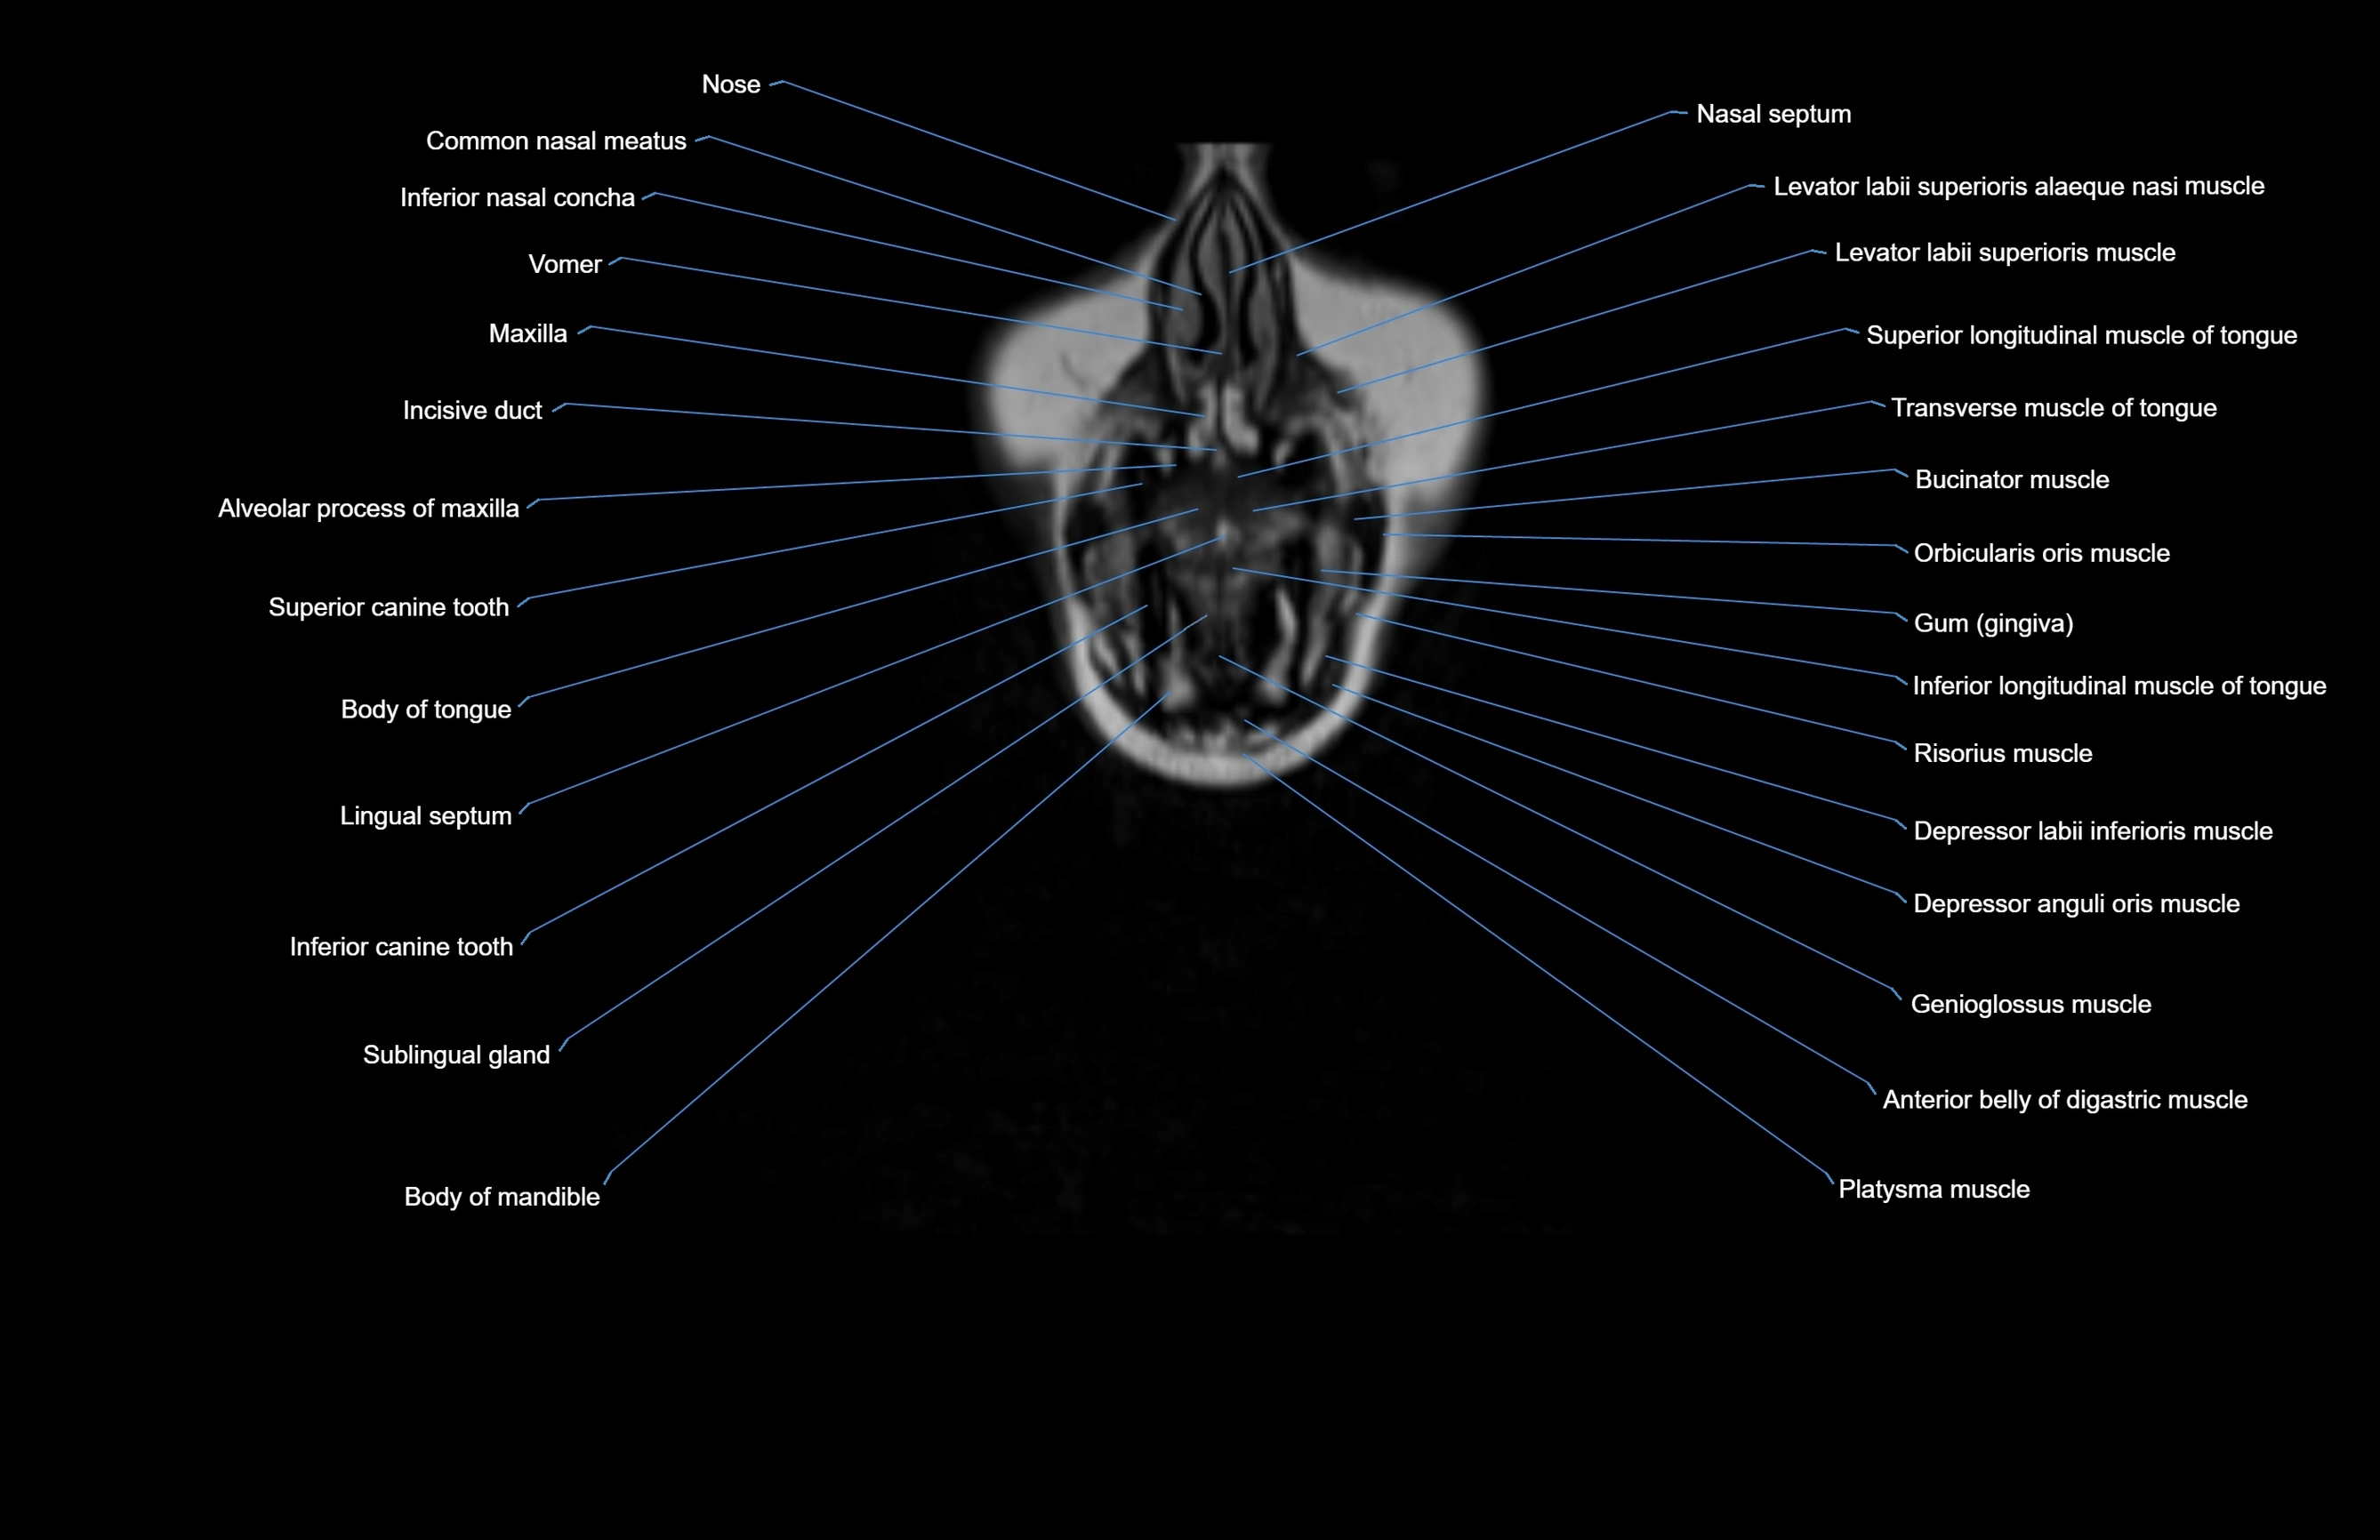

- Alveolar process of maxilla

- Anterior belly of digastric muscle

- Body of mandible

- Body of tongue

- Buccinator muscle

- Common nasal meatus

- Depressor anguli oris muscle

- Depressor labii inferioris muscle

- Genioglossus muscle

- Gum (gingiva)

- Incisive duct

- Inferior canine tooth

- Inferior longitudinal lingual muscle

- Inferior longitudinal muscle of tongue

- Lingual Septum

- Maxilla

- Nasal septum

- Orbicularis oris muscle

- Platysma muscle

- Risorius muscle

- Sublingual gland

- Superior longitudinal muscle of tongue

- Transverse muscle of the tongue

- Transverse muscle of tongue

- Vomer